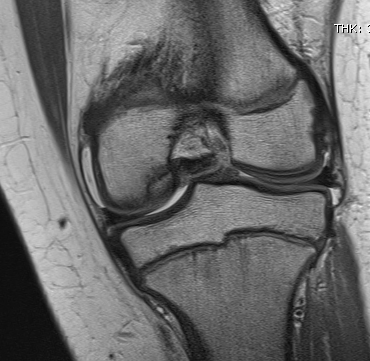

- sickling occurs with relative hypoxia

- trapped in blood vessels

- necrosis & pain